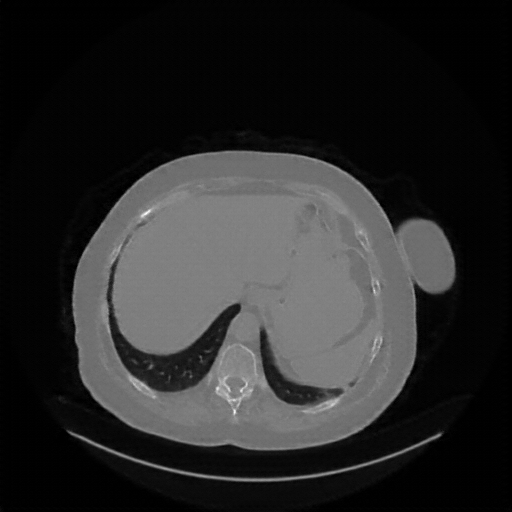

Original NATIVE CT scan (input)

Full window (WL 1023.5, WW 4095 β†’ Low βˆ’1024, High +3071)

Lung window (WL -600, WW 1500 β†’ Low βˆ’1350, High +150)

Mediastinum window (WL 40, WW 400 β†’ Low βˆ’160, High +240)